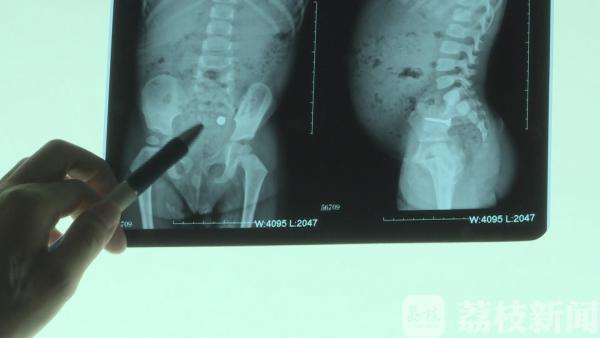

5月24号早上,乐乐的妈妈胡女士发现儿子在把玩一根螺丝钉,就在她上前阻止的瞬间,乐乐将螺丝钉吞了下去。经过检查,乐乐状态不错,腹部没有明显压痛、反射痛,体温和血象也都正常。医生没有贸然选择手术,而是让乐乐留院观察,每隔一段时间拍摄一张X光片。小孩入院12小时后再次复查腹部立位片, 发现螺丝钉的位置已经比之前明显的下降, 大概到了大肠的位置, 但是这个螺丝钉方向仍然随时有可能会划破大肠的肠管壁 。

尽管螺丝钉的位置在下移,但毕竟十分尖锐,伴随肠道蠕动,随时有可能发生位置偏移,划破肠壁导致严重的腹膜炎,不及时治疗是致命的。但是为了尽可能避免手术给孩子带来的创伤,医生还是决定继续观察。最后一次复查腹部立位片, 发现这个螺丝钉已经进入盆腔 ,进入了直肠部 ,医生决定用开塞露给他通便 ,通过开塞露灌肠之后 ,很幸运的是,这名小男孩体内的螺丝钉排了出来。